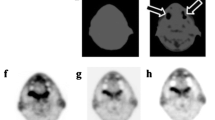

Although the 18F-FDG is the most commonly used radiotracer in PET studies, its specificity and sensitivity are notably reduced in the brain region. As a matter of fact, 18F-FDG is a glucose metabolism tracer whose distribution involves cells according to the glucose transport mechanism and, consequently, it is not limited to malignant tissue, i.e. 18F-FDG PET can be limited by unspecific uptake in inflammatory benign lesions [40]. In [41], 18F-FDG shows limited clinical value when comparing brain tumour volume defined by metabolic imaging with the corresponding volume defined by PET/MRI images due to low contrast between tumour and healthy tissue in 18F-FDG PET images. Vice versa, 18F-FDG PET may be useful in distinguishing common enhancing malignant brain tumours, particularly high grade and low-grade gliomas and lymphoma [42,43,44]. Nevertheless, a high 18F-FDG uptake in surrounding healthy tissue limits its use for the imaging of a large fraction of primary and recurrent tumours [45]. For example, glioblastoma shows glucose uptake higher than in anaplastic astrocytoma that, vice versa, shows hypo-metabolism. This difference could be explained by the presence of necrosis [46]. In conclusion, 18F-FDG PET often poses a challenge in the identification of treatment-induced necrosis, edema, inflammation, and pseudo-progression. For this reason, other PET radiotracers have been developed, i.e. 11C-MET that shows excellent sensitivity and specificity in the detection of brain metastases [21, 22, 35]. Thanks to the injected 11C-MET radiotracer, metastasis appears as a hyperintense region. Unfortunately, 11C-MET PET is not widespread in clinical practice due to very short half-life of 11C (around 20 min) requiring a short interval between synthesis, injection, and acquisition. Consequently, only the medical centres which have an onsite cyclotron can utilize 11C-MET radiotracer. Alternatively, [18F]fluoro-ethyl-l-tyrosine (18F-FET) significantly correlates with brain tumour cell density and proliferation [40] and it can be distributed to PET centres without a cyclotron unit on site (18F half-life = 110 min).

The fully automatic segmentation method

In the proposed method, PET images were pre-processed as previously described by our group [47]. Precisely, the body-weight SUV, the most widely used PET parameter, was used to convert PET images into SUV unit (g/ml) images. Successively, to obtain a fully automatic BTV segmentation system starting from the one proposed [27], our algorithm performs all segmentation steps automatically by individuating an optimal, operator-independent, initial ROI located around the tumour on an automatically selected PET slice. By taking advantage of the great sensitivity and specificity of 11C-MET radio-tracers in discriminating between healthy and tumour tissues, the system identifies the PET slice containing the maximum SUV (SUVmax) in the whole PET dataset avoiding any user intervention. Consequently, the SUVmax voxel is used as a target seed for a region growing segmentation [18] to automatically identify a ROI containing the lesion. It is worth noting that the region growing algorithm is used only to obtain a rough estimate of the lesion boundary. This initial operator-independent ROI is input to the next component of the system, an enhanced LAC segmentation algorithm [48], as extensively explained [27]. Despite the LAC method is able of locally widening or tightening around the lesion boundary, a stopping criterion has been implemented to prevent wrong segmentations when a free disease slice is reached. This because the LAC algorithm is driven by the image properties rather than by an inherent knowledge of whether the tumour is present. In other words, the LAC is automatically stopped when a free disease PET slice is reached [27]. In this way, the proposed system becomes fully automatic for the segmentation of brain metastases in 11C-MET PET images [29]. In the case of multiple brain metastases, each lesion is independently processed. A different local maximum (SUVmax-j, with j = 1:n) is identified for each lesion. By design, the first BTV contains global SUVmax. The delineation iterative procedure ends when the SUVmax of the currently processed lesion is less than 2 g/ml. However, the user will receive a warning message in case of multiple lesions and will be able to stop the process to avoid false-positive occurrences (healthy tissues with SUVmax > 2 g/ml).